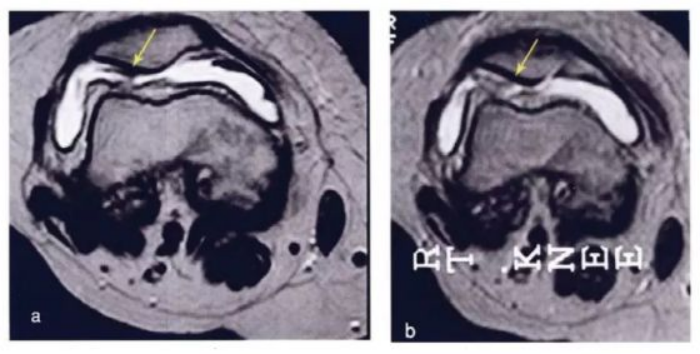

下图是治疗前后的核磁对比,,如之前的一样,,,颜色越蓝,,,代表软骨质量越好。。可以看出间充质干细胞治疗后软骨质量明显提高。。